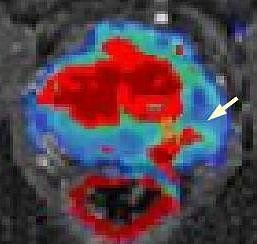

MRT von Prostata (Foto: SHK)

Bei diesem Jahrestreffen der nordamerikanische Röntgengesellschaft, an dem 65.000 Fachleute teilnehmen, wird der Nordhäuser Mediziner über die MR-gestützte Abklärung von auffälligen Befunden an der Prostata referieren. Das Nordhäuser Krankenhaus ist eines von sehr wenigen Häusern in Deutschland und bislang das einzige in Thüringen, das diese interventionelle Methode anbietet (siehe Foto, Pfleil zeigt auf Karzinom). In diesem Zusammenhang besteht seit längerem eine enge Zusammenarbeit mit dem Fraunhofer-Institut in Bremen.

Wenn bei einem Tumorverdacht die ultraschallgestützte Biopsie der Prostata keinen Tumornachweis erbringt, kann die MRT-basierte Biopsie als zweite Option angewandt werden. Der Vortrag befaßt sich mit den nötigen Vorbereitungen und der benötigten Hardware, der Planung der Biopsie, der Durchführung, möglichen Komplikationen und den histologischen Ergebnissen im Vergleich zu den ursprünglichen Bildcharakteristika im MRT.

Hierbei hat sich eine Kooperation mit niedergelassenen urologischen Kollegen in Nordthüringen und Sachsen-Anhalt herausgebildet, die folgerichtig auch Koautoren dieses Vortrags sind. Die MR-gestützte Biopsie ist vom Nordhäuser radiologischen Team inzwischen bei mehr als 50 Patienten im Südharz-Krankenhaus bereits erfolgreich angewandt worden und daraus konnten Erkenntnisse für die weitere Arbeit gewonnen werden, die nun vorgestellt werden.